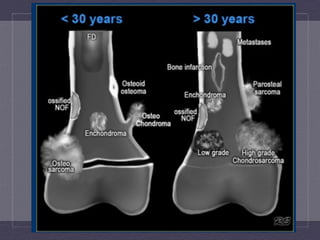

ENCHONDROMA  VS  LOW  GRADE  CHONDROSARCOMA